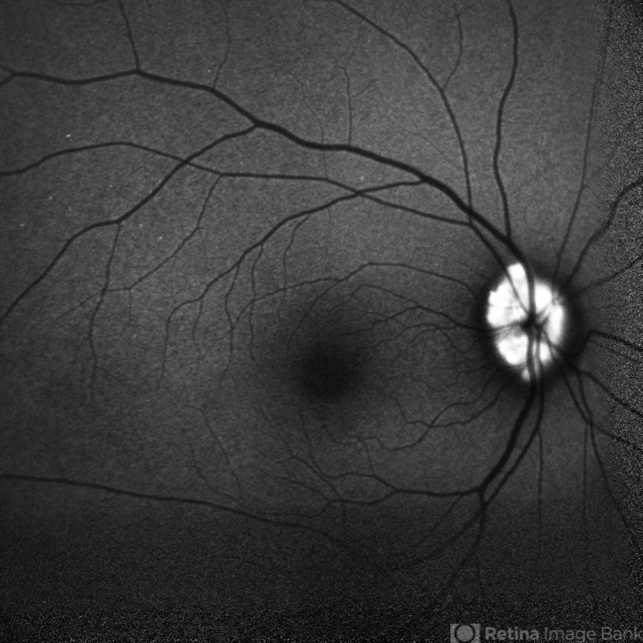

- drusen of optic disc

Scanning laser ophthalmoscope

Mirante - Description

- FAF photograph of RE of a 32 year old female with Optic nerve head drusen